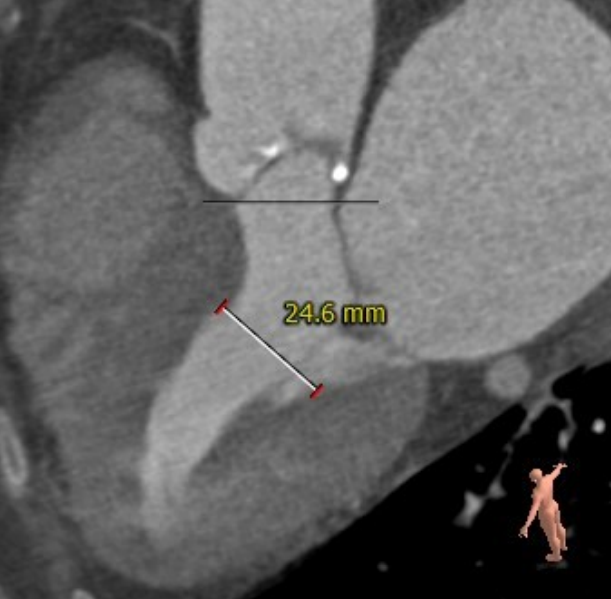

CT评估报告

瓣环平均直径:21.0 mm,左室流出道平均直径:22.6 mm

升主动脉未见明显扩张,心脏角度:46°

左冠高度:13.1 mm,瓣叶长度:18.0 mm;右冠高度:16.7 mm,瓣叶长度:17.3 mm

心腔较小,心肌较厚,主动脉弓部角度平缓

术前CT测量与冠脉风险评估